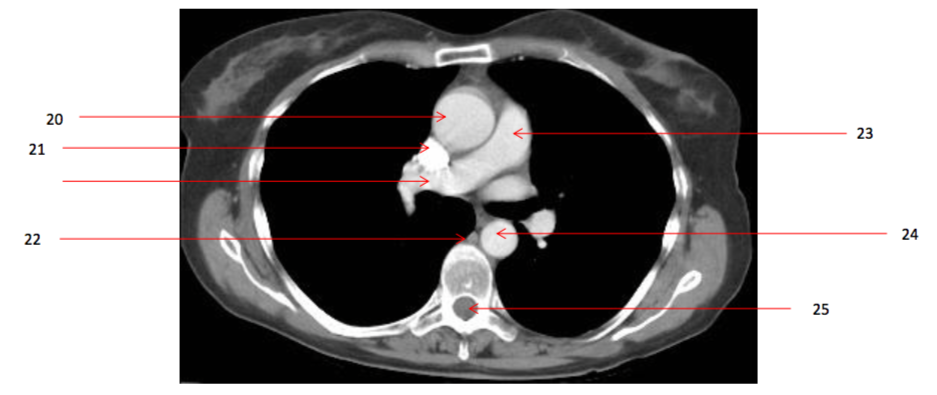

Number 20?

Ascending aorta

Number 23?

Pulmonary trunk

Q

Number 21?

23

Number 22?

24

Number 29?

Azygos vein

Number 27?

SVC

Number 28?

Rt pulmonary vein

Number 25?

Spinal injury

Number 24?

Descending thoracic aorta